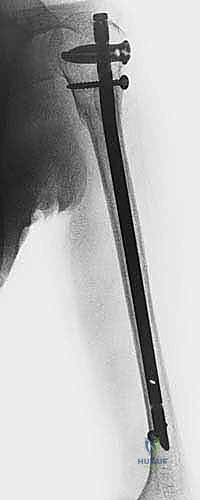

6. القفل الديناميكي والاستاتيكي (Locking):

لمنع المسمار من الدوران أو الانزلاق، يجب تثبيته ببراغي عرضية. يتم إدخال البراغي العلوية في الكتف عبر جهاز توجيه متصل بالمسمار. أما البراغي السفلية (فوق الكوع)، فتتطلب مهارة فائقة؛ حيث يتم إدخالها عبر شقوق صغيرة جداً (1 سم) باستخدام تقنية "اليد الحرة" (Freehand Technique) تحت توجيه الأشعة، مع حماية العصب الكعبري والأوعية الدموية بدقة.

* الشكل القمعي المتغير: الثلثان العلويان من قناة العضد يتميزان بشكل أسطواني وواسع نسبياً، لكن القناة تتضيق بشكل حاد وسريع في الثلث السفلي لتصبح صلبة جداً. هذا التباين الهندسي يجعل تحقيق "التثبيت التداخلي" (Interference fit) - أي أن يثبت المسمار نفسه بمجرد حشره في العظم - أمراً شبه مستحيل. لذلك، أصبح استخدام "البراغي القابلة للقفل" (Locking Screws) في أعلى وأسفل المسمار هو المعيار الذهبي العالمي الذي يطبقه الأستاذ الدكتور محمد هطيف لضمان عدم دوران العظم أو تحركه بعد الجراحة.